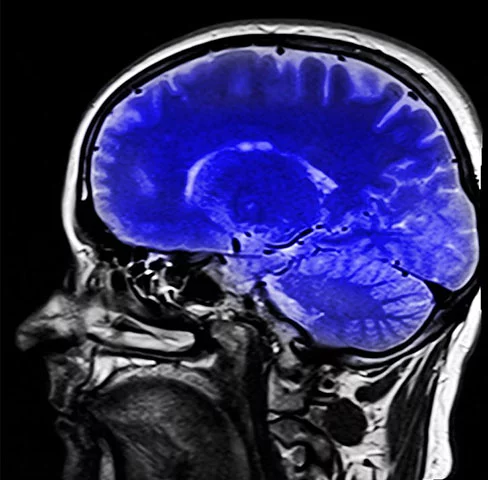

Estudo alerta: remédios para dormir podem aumentar risco de demência